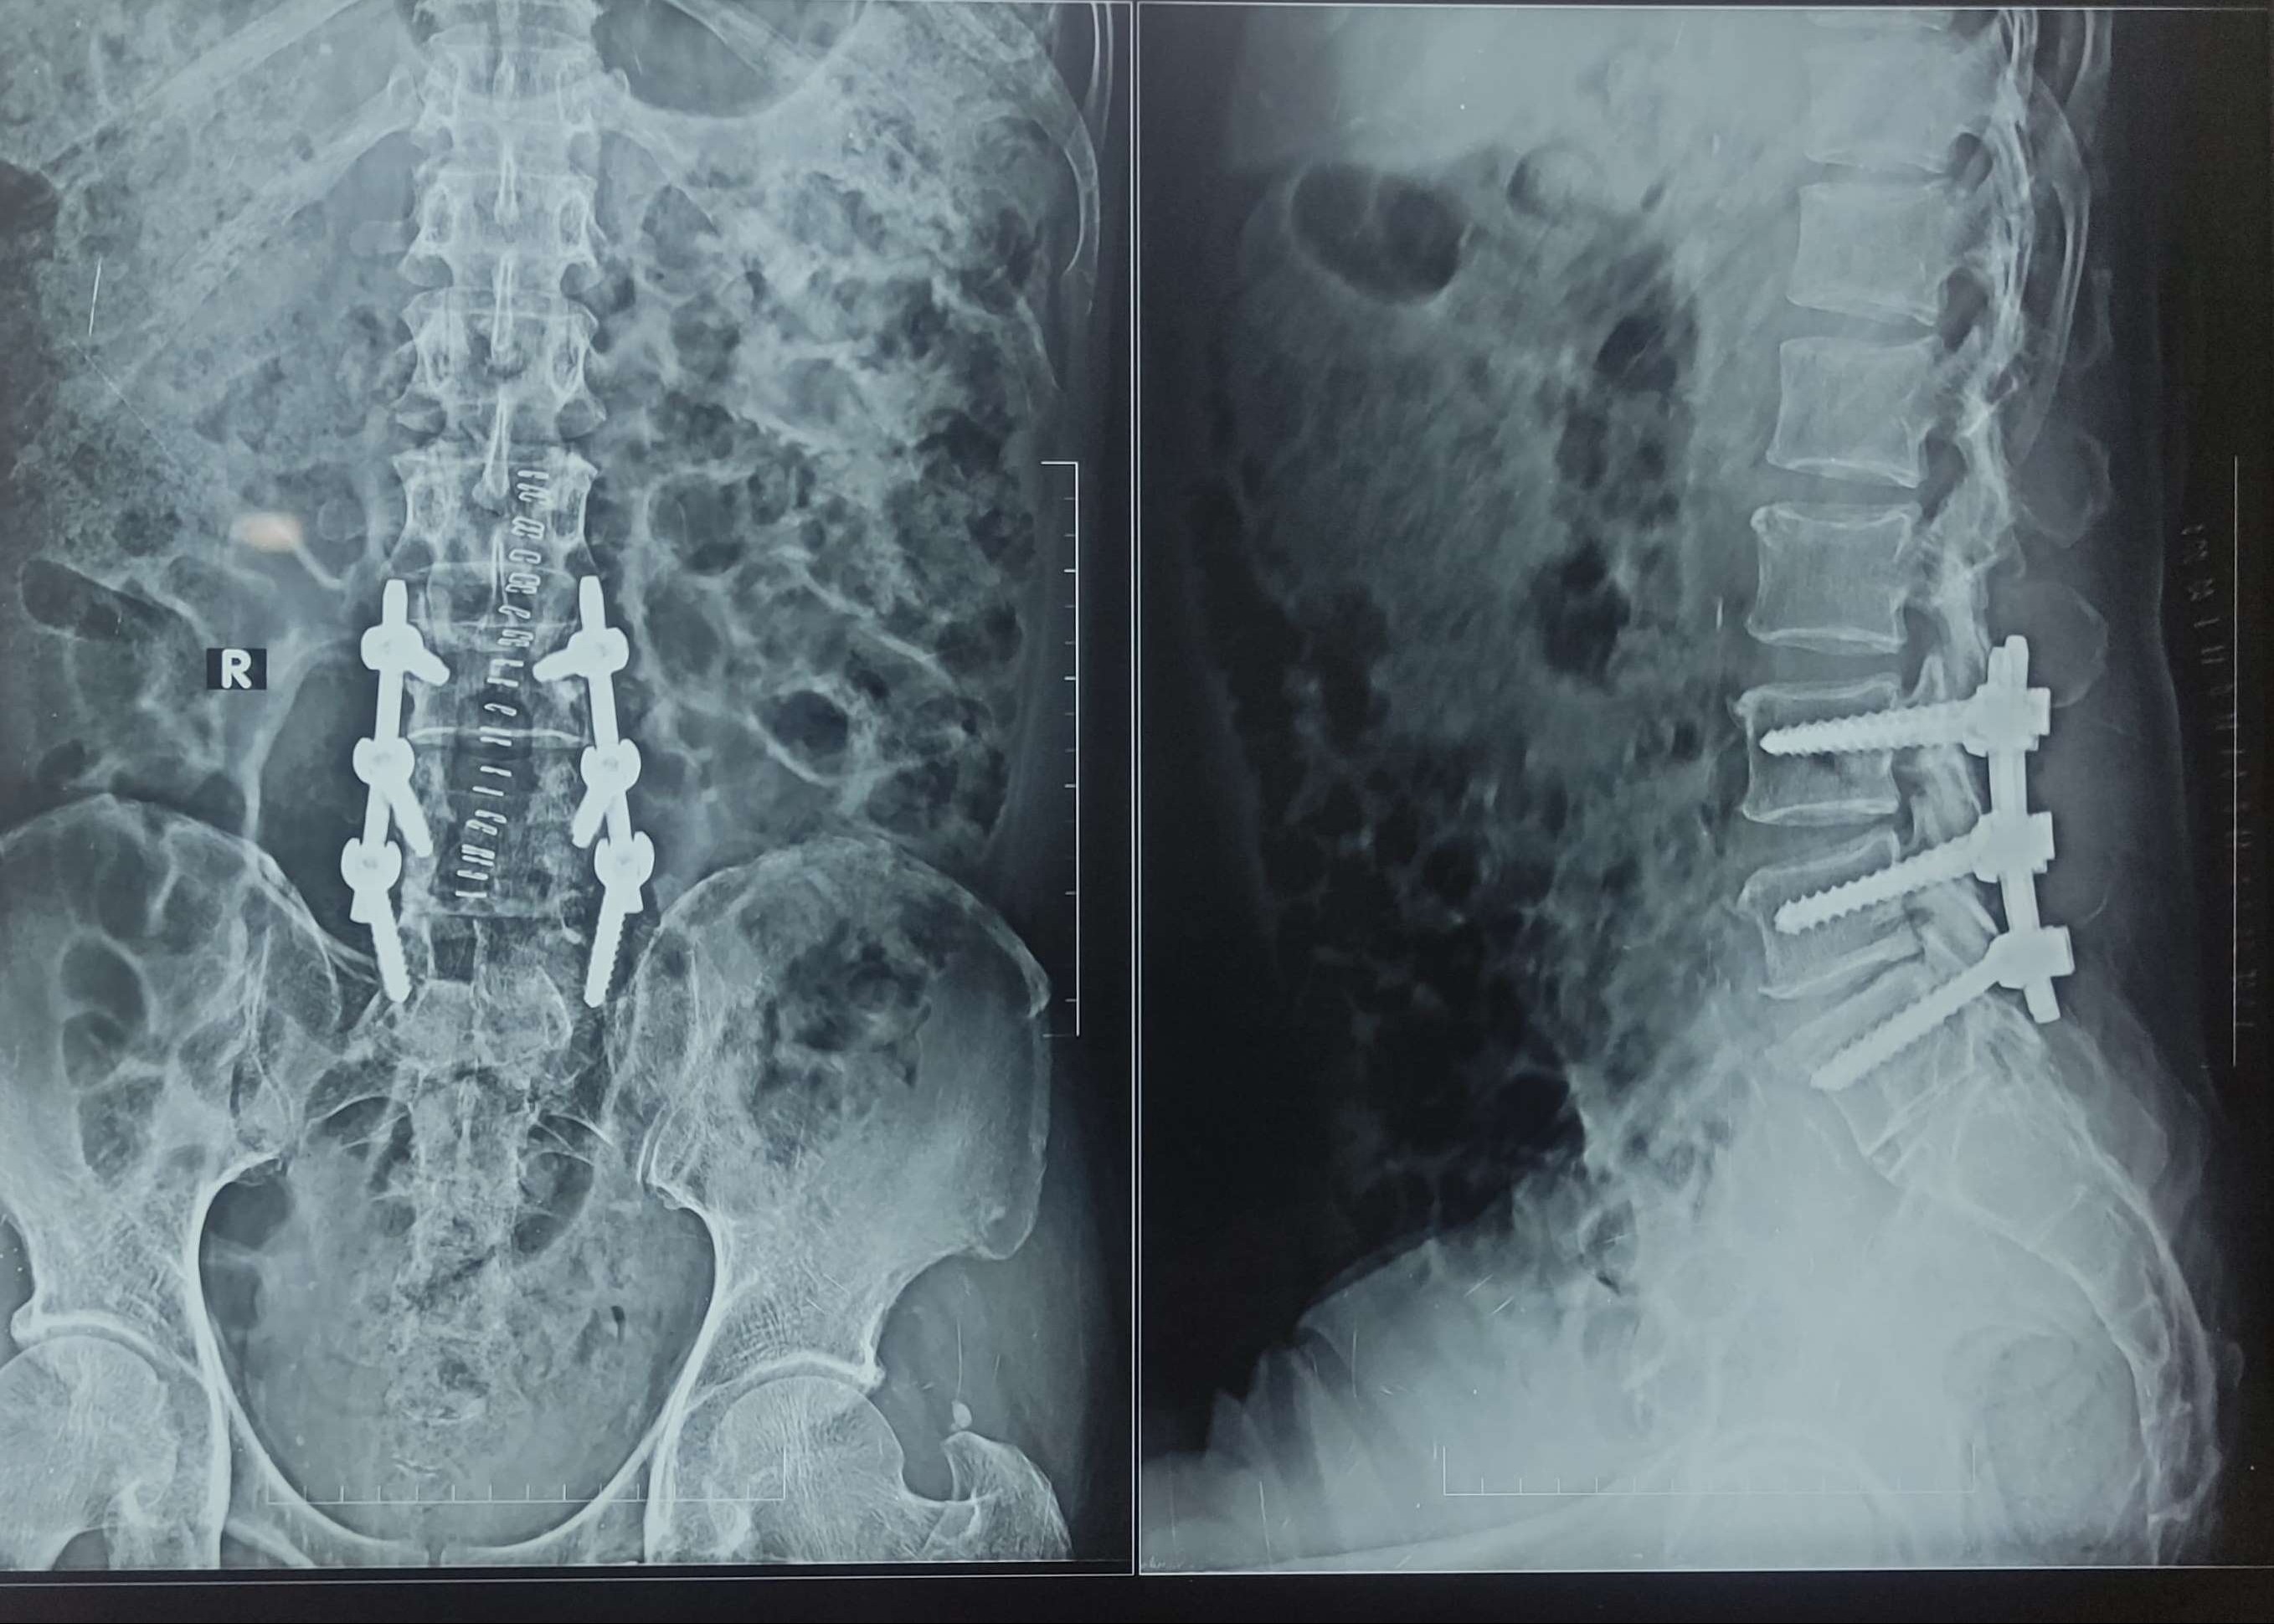

Dr. Nitish Agarwal - BEST SPINE SURGEON IN PUNE Neck pain/Back pain treatment/Spine Specialist in Pune /Microscopic Surgeon Patient Condition A 60-year-old patient presented with:- Severe lower back pain Inability to walk Right leg weakness Tingling sensation, heaviness and severe radiating leg pain Symptoms typical of lumbar disc herniation with nerve root compression MRI Findings :- MRI revealed: L3-L4 and L4-L5 disc prolapse Severe spinal canal stenosis Compression of the nerve roots This confirmed advanced lumbar disc disease requiring surgical decompression. Surgical Procedure Performed L3-L4, L4-L5 Microdiscectomy & Decompression Laminectomy with Posterior Spinal Fixation (A minimally invasive spine surgery technique / MICROSCOPIC SURGERY) The surgery included: Microdiscectomy at L3-L4 and L4-L5 levels Laminectomy for spinal canal decompression Removal of pressure from compressed nerve roots Stabilization using best quality titanium screws and rods for long-term spine stability All steps completed using microscopic and minimally invasive spine surgery techniques Post-Surgery Results The patient showed excellent recovery, including:- Walking comfortably from the next day with a lumbar belt Leg pain completely relieved No tingling or numbness in lower limbs Improved mobility and sitting comfort Advised to continue post-operative spine strengthening exercises